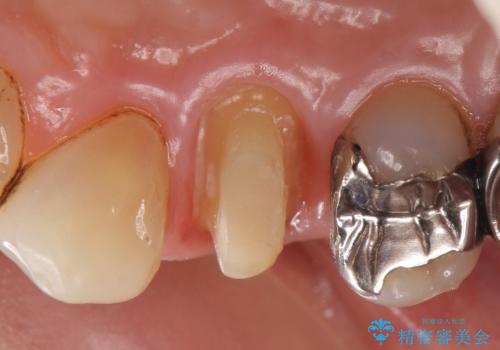

検査の結果持続痛も認めたため、虫歯除去後根管治療を行いました。

その後オールセラミッククラウン(エクセレント)による補綴を行いました。

- オールセラミッククラウン(エクセレント)…¥180,000、仮歯…¥10,000、ファイバーコア…¥20,000費用は治療当時の料金となります